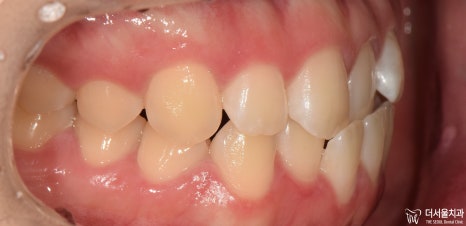

『인비절라인 기간 ’10개월’간의 기록 (초진)』

“저 입이 툭 튀어나와서 좀 집어넣고 싶어요.

근데 눈에 잘 띄는 철사들은 부담스럽더라고요.”

어?

아랫니가 윗니를 덮고 있는

‘반대교합(cross bite)’이 함께 나타나고 있군요.

정중선이 맞지 않는 것은 물론이며

전치부 치열에서 총생(crowding)도 함께 동반되었습니다.

이와 더불어,

전방으로 돌출되어 있는 모습이 관찰되네요.